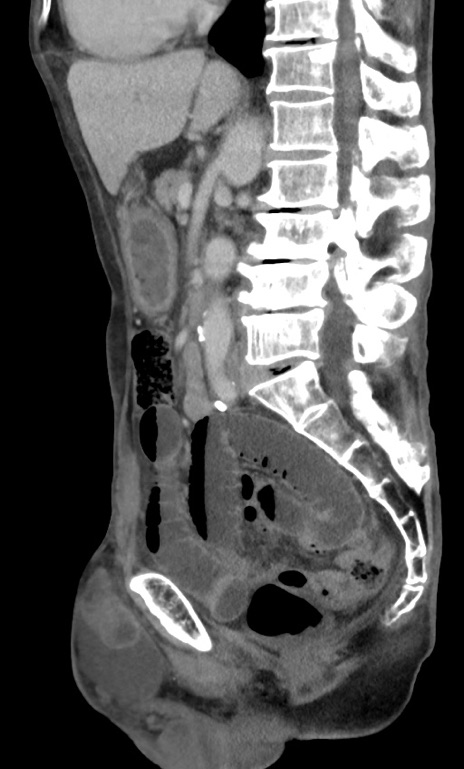

症例3(矢状断像)

【症例】 70歳代男性

【主訴】右鼠径部腫瘤、疼痛

【現病歴】本日朝より上記主訴あり、受診。

【既往歴】膀胱癌にて膀胱全摘、両側尿管皮膚瘻

【データ】WBC 5600、CRP 0.56